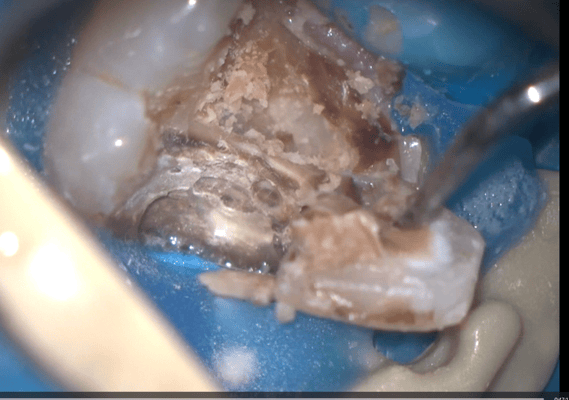

写真はすべてミラー像です。上顎左側側切歯遠心面の大きな虫歯です。エキスカで丁寧に軟化象牙質を除去していくと、歯髄腔まで本当に皮一枚になりました。血流が見えるようです。エキスカから伝わる組織の硬軟の感覚と対物-接眼レンズからの像が ”皮一枚”を達成できたと思います。皮一枚ですが、硬組織は残っていますので、ティース・プライマーを塗布し、スーパーボンド・ラジオオペークとバルクベースにて覆髄をしました。もちろん、1ケ月後の歯髄診でも陽性反応を示し、歯髄は生きています。

メタルインレー下にはレジンの覆髄が施されていましたが、接着しておらず、ポロリと取れました。これが、2次齲蝕(治療後の虫歯の再発)の原因です。多量の軟化象牙質(虫歯)を除去していくと、歯髄腔(神経と血管が入っている部屋)まで紙一枚。うっすら赤い血流も確認できます。齲蝕除去中に口蓋側の咬頭が破折しましたので、グラスファイバーポストによって、生活歯の支台築造。神経も取らずに残せる歯は、本当に多くあります。